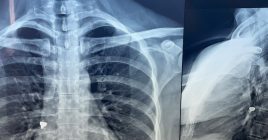

Ministri i Shëndetësisë, Arben Vitia, Ambasadori i Turqisë në Kosovë, Tunç Angili dhe drejtori i përgjithshëm i Shërbimit Spitalor dhe Klinik Universitar, Elvir Azizi, kanë mirëpritur të hënën ekipin e mjekëve dhe ekspertëve nga Turqia, të cilët gjatë javës do të kryejnë 16 operacione kardiokirurgjike tek fëmijët me probleme në zemër si dhe do të realizojnë 30 intervenime të tjera kardiologjike, përfshirë koronarografi dhe stentime dhe raste elektrofiziologjike.